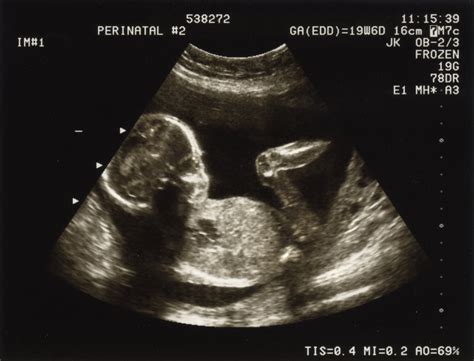

- Ecografii (abdominală, transvaginală, mamară, Doppler 2D/3D/4D)

- Monitorizarea sarcinii pe trimestre (I, II, III)